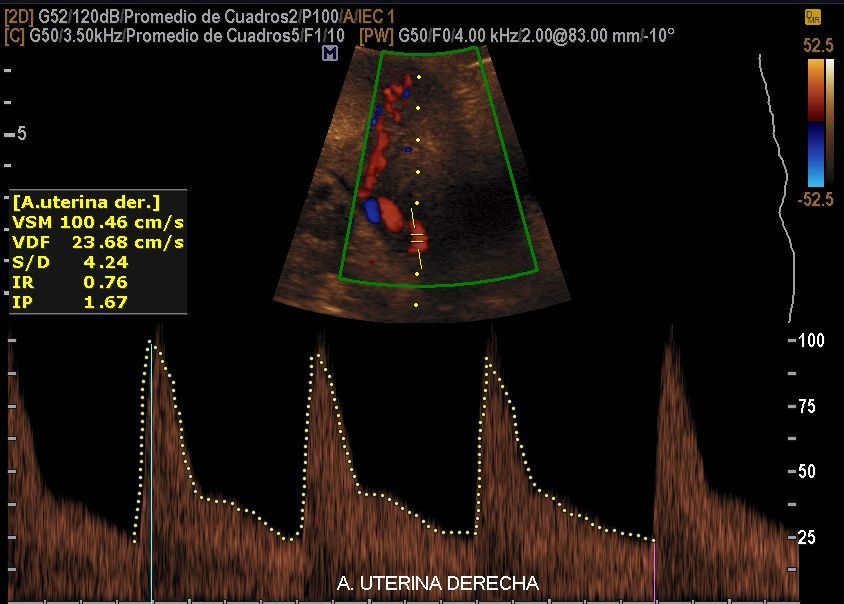

Servicios Ecográficos de Alta Calidad

Realizamos las ecografías de viabilidad del embarazo, genética, morfológica, de bienestar fetal, ecocardiografías fetales, así como procedimientos invasivos como biopsia de vellosidades coriales y amniocentesis.